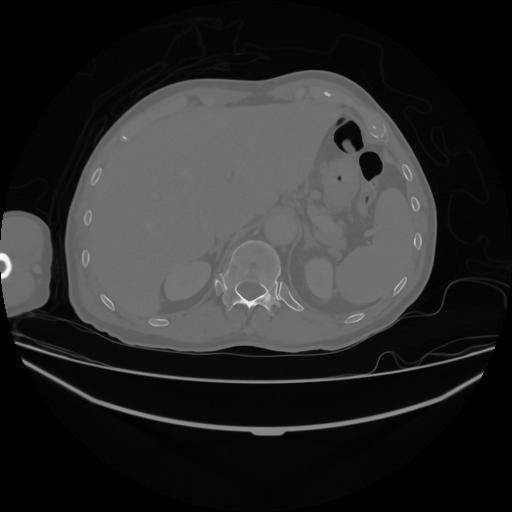

5 CUERPO,CE,Vol,1.0,CUERPO,,